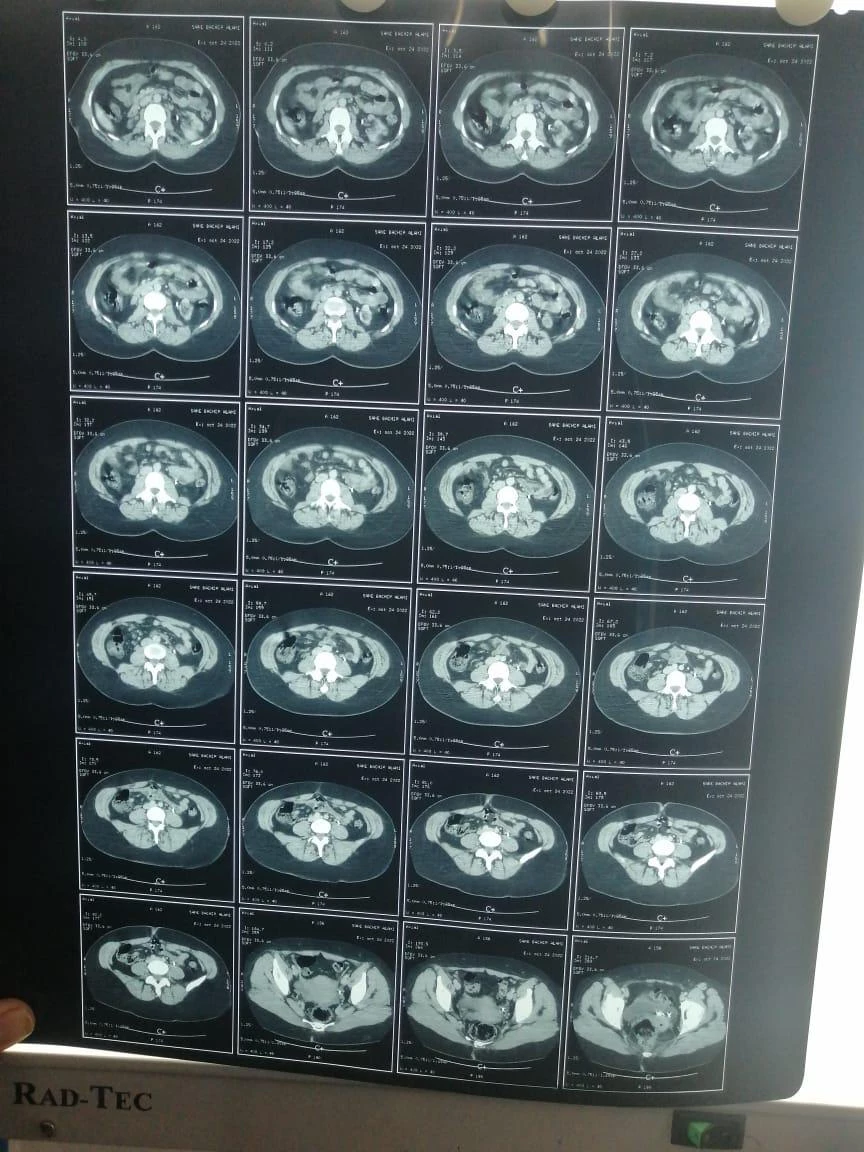

Sanae sufre varias enfermedades, entre ellas insuficiencia renal crónica, cálculos biliares y una hernia discal, que hacen que su día a día esté marcado por el dolor. Estas enfermedades requieren medicación constante, análisis de sangre frecuentes y diversas intervenciones médicas.